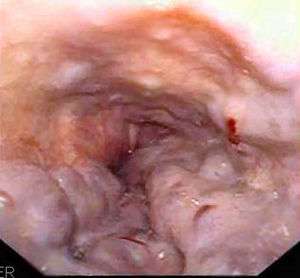

| Gastroscopy image of esophageal varices with prominent cherry-red spots | |

In medicine (gastroenterology), esophageal varices (or oesophageal varices) are extremely dilated sub-mucosal veins in the lower third[1] of the esophagus. They are most often a consequence of portal hypertension, commonly due to cirrhosis; patients with esophageal varices have a strong tendency to develop bleeding.

Esophageal varices are diagnosed with endoscopy.[2]

Dilated submucosal veins are the most prominent histologic feature of esophageal varices. The expansion of the submucosa leads to elevation of the mucosa above the surrounding tissue, which is apparent during endoscopy and is a key diagnostic feature. Evidence of recent variceal hemorrhage includes necrosis and ulceration of the mucosa. Evidence of past variceal hemorrhage includes inflammation and venous thrombosis.